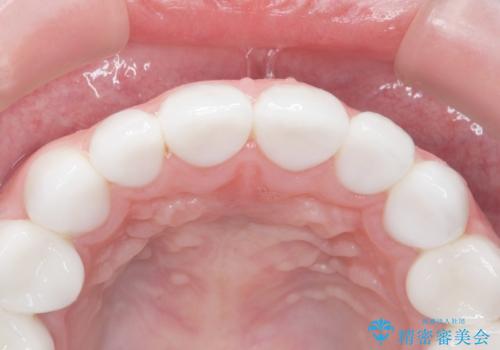

- K-POP(Kポップ)アイドルのような歯にしたいと希望され来院された患者様です。

矯正を途中でやめてしまったとのことで、歯に矯正の接着材が残っており着色も顕著でした。

奥歯の咬合面にはレジンが盛られた状態でした。

見た目と咬み合わせを改善するため、セラミッククラウンによる治療を行いました。

綺麗な仕上がりにご満足下さいました。

奥歯の咬み合わせも良くなったと喜んで頂けました。

患者様の理想とする韓流アイドルの写真を技工士さんに送り、最終的なクラウンの形や色をできるだけ理想に近づけられるよう努めました。

クラウンの種類:オールセラミッククラウン スタンダード